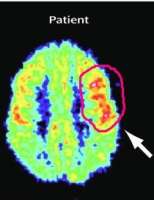

Меня вот например ещё интересует в каком поле по бродману дп/др локализируется и какую роль в этом всём может играть генетика.

Да-да видел, кстати в фмрт и ПЭТ исследованиях видна одна корреляция на счёт чрезмерной активации 47-го поля бродмана, правда я не знаю на что реагировали пациенты в ПЭТ исследовании.